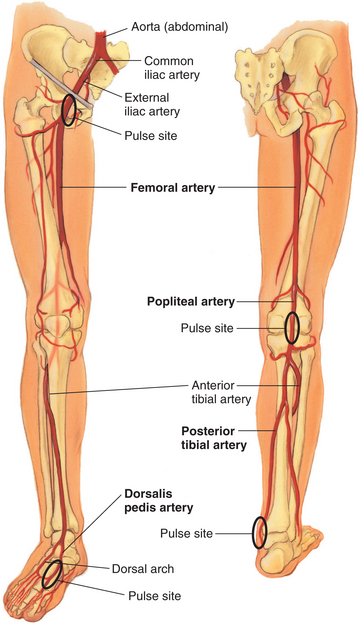

Figure 12-30 Arteries in the leg. The abdominal aorta branches (aortic bifurcation) into the right and left common iliac arteries. These arteries pass through the pelvic cavity and under the inguinal ligament to become the major arteries supplying the leg, called the femoral arteries. Each femoral artery travels down the thigh until, at the lower thigh, it courses posteriorly, where it becomes the popliteal artery. Below the knee, the popliteal artery divides into the anterior tibial artery and posterior tibial artery. The anterior tibial artery travels down the front of the leg onto the dorsum of the foot, where it becomes the dorsalis pedis artery. In the back of the leg, the posterior tibial artery travels down behind the malleolus and forms the plantar arteries in the foot. (From Jarvis C: Physical examination and health assessment, ed 5, Philadelphia, 2008, Saunders.)